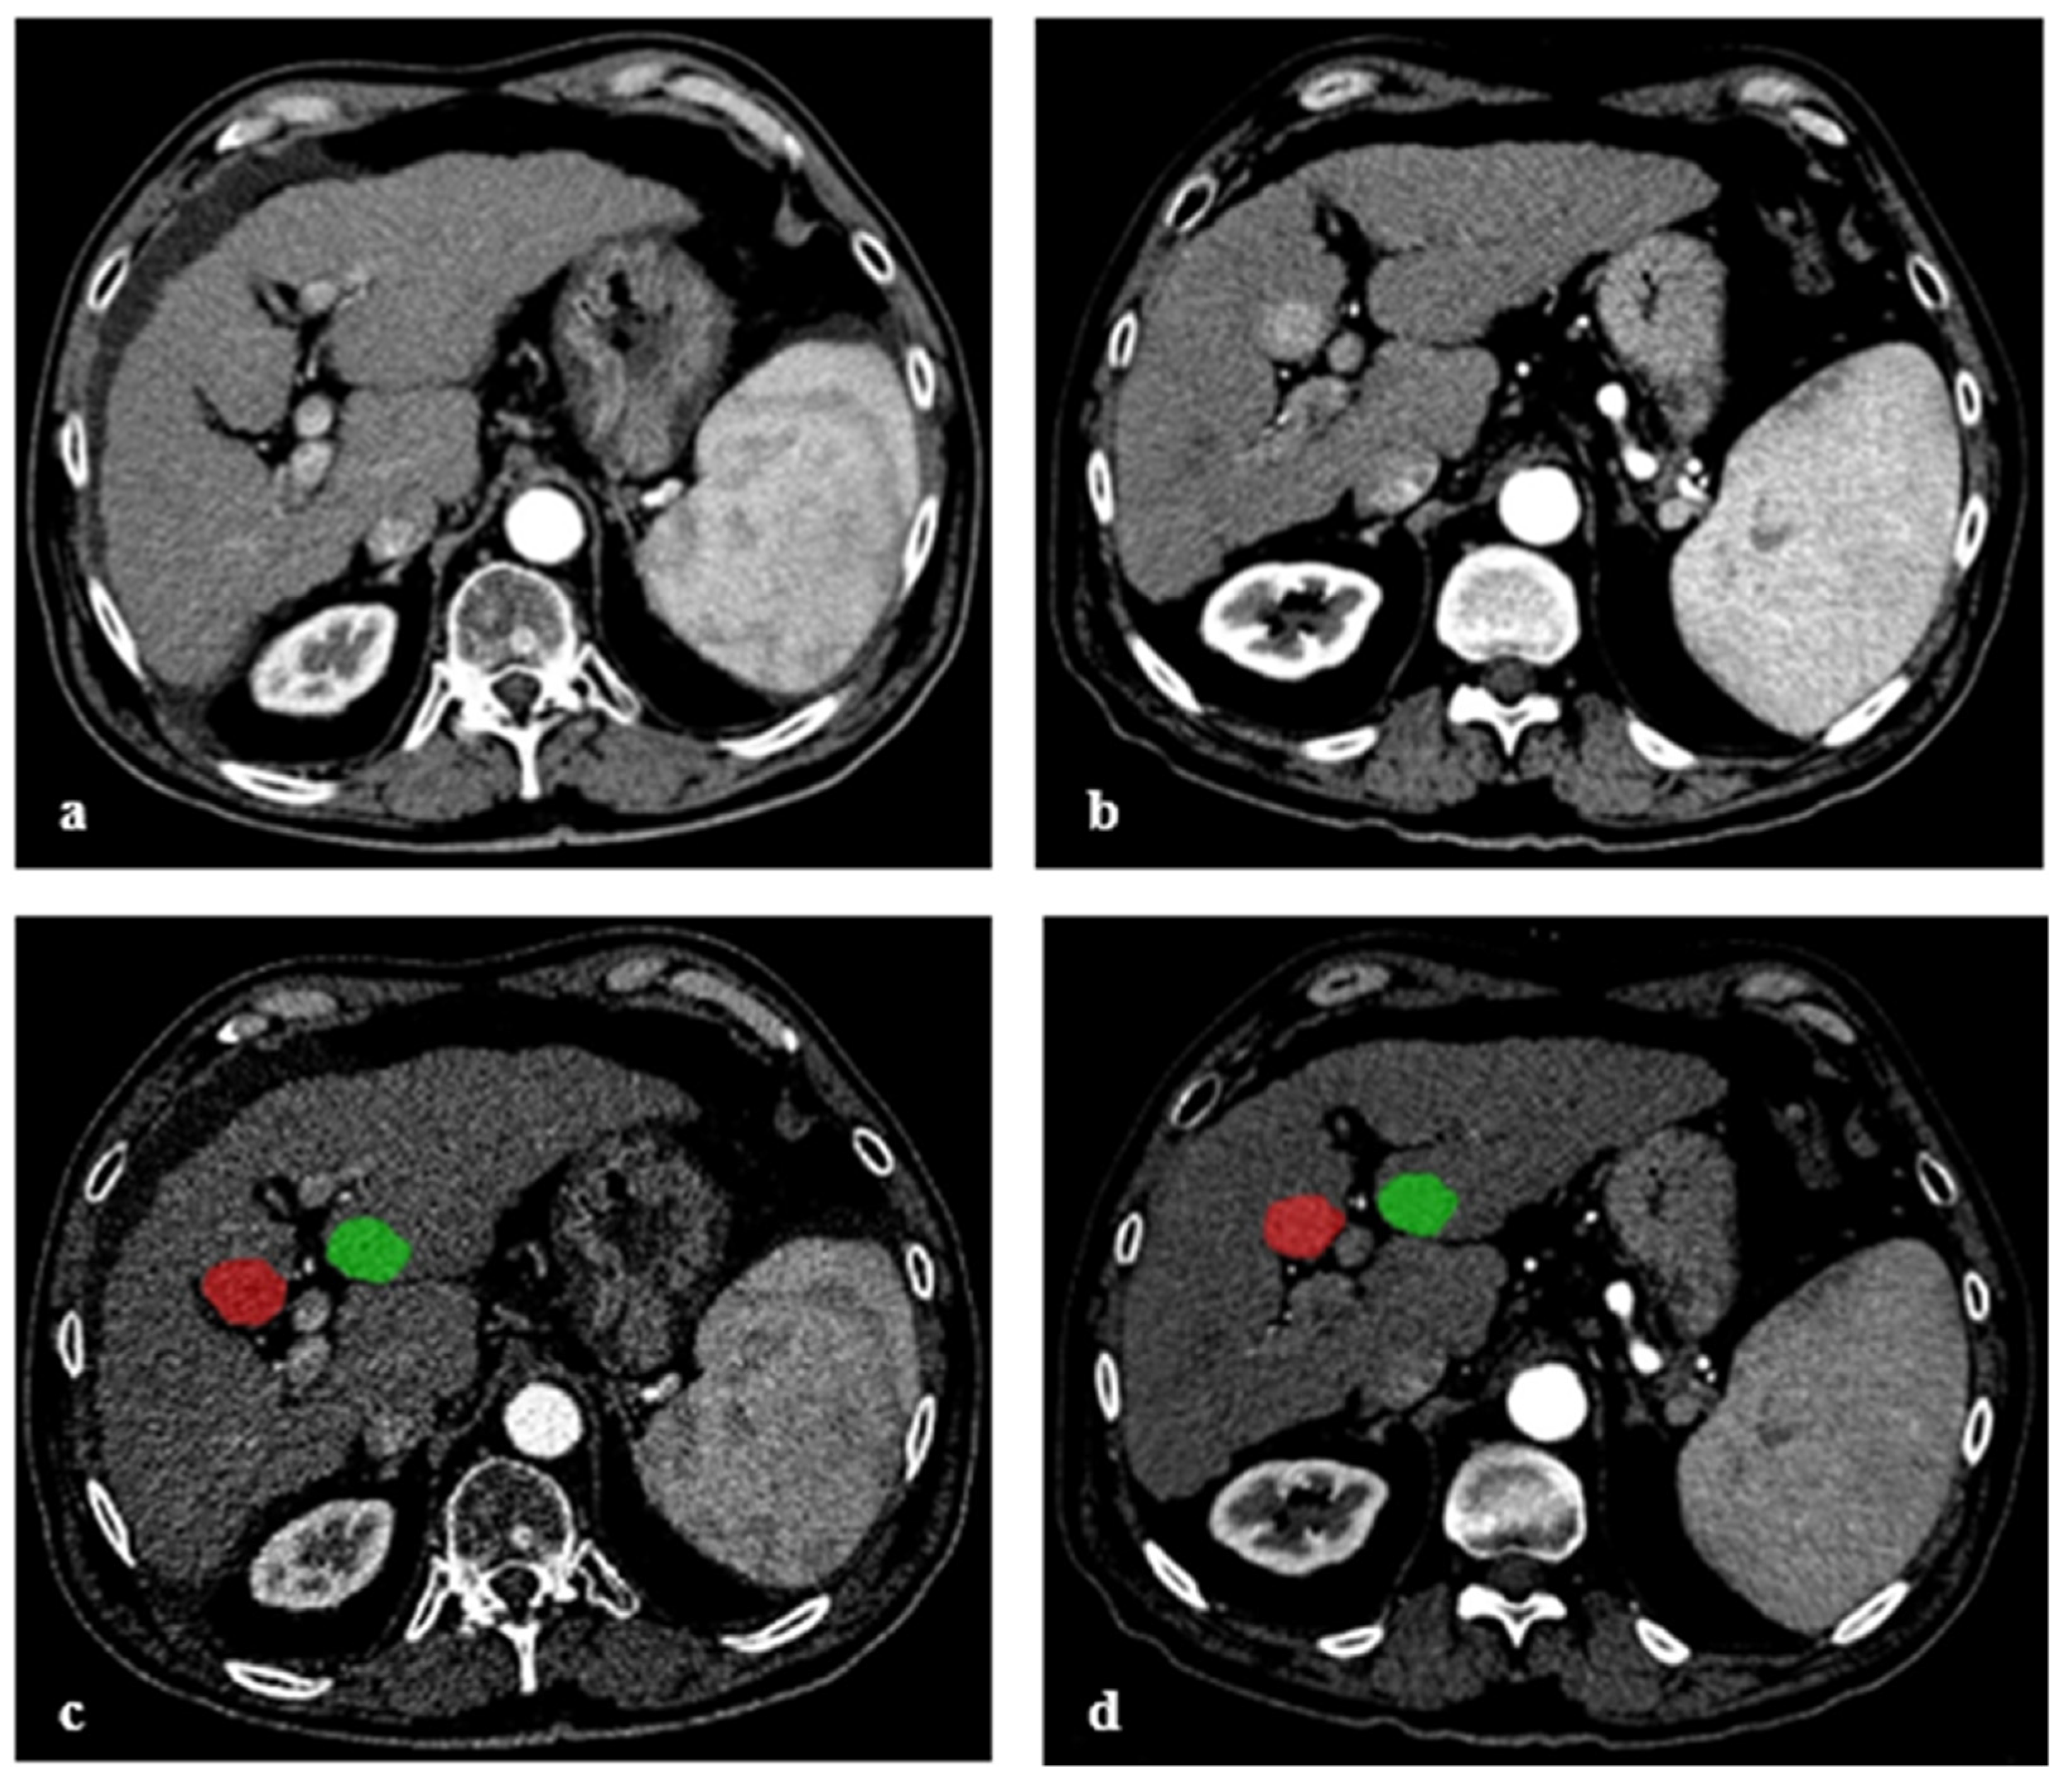

Figure 2.

Arterial phase computed tomography of a cirrhotic patient with no visually detectable lesion on initial CT (PRE-CT) (a). CT 6 months later (FU-CT) shows a newly emerged HCC lesion in liver segment V (b). Segmentations used for the analysis in arterial phase images of PRE-CT (c) and FU-CT (d). Segmentations were first drawn around the visible border of HCC in FU-CT and subsequently in the corresponding region in PRE-CT, shown in red. As a negative control, a segmentation comparable in size and shape was drawn in PRE-CT and FU-CT in a region without manifestation of HCC, shown in green.